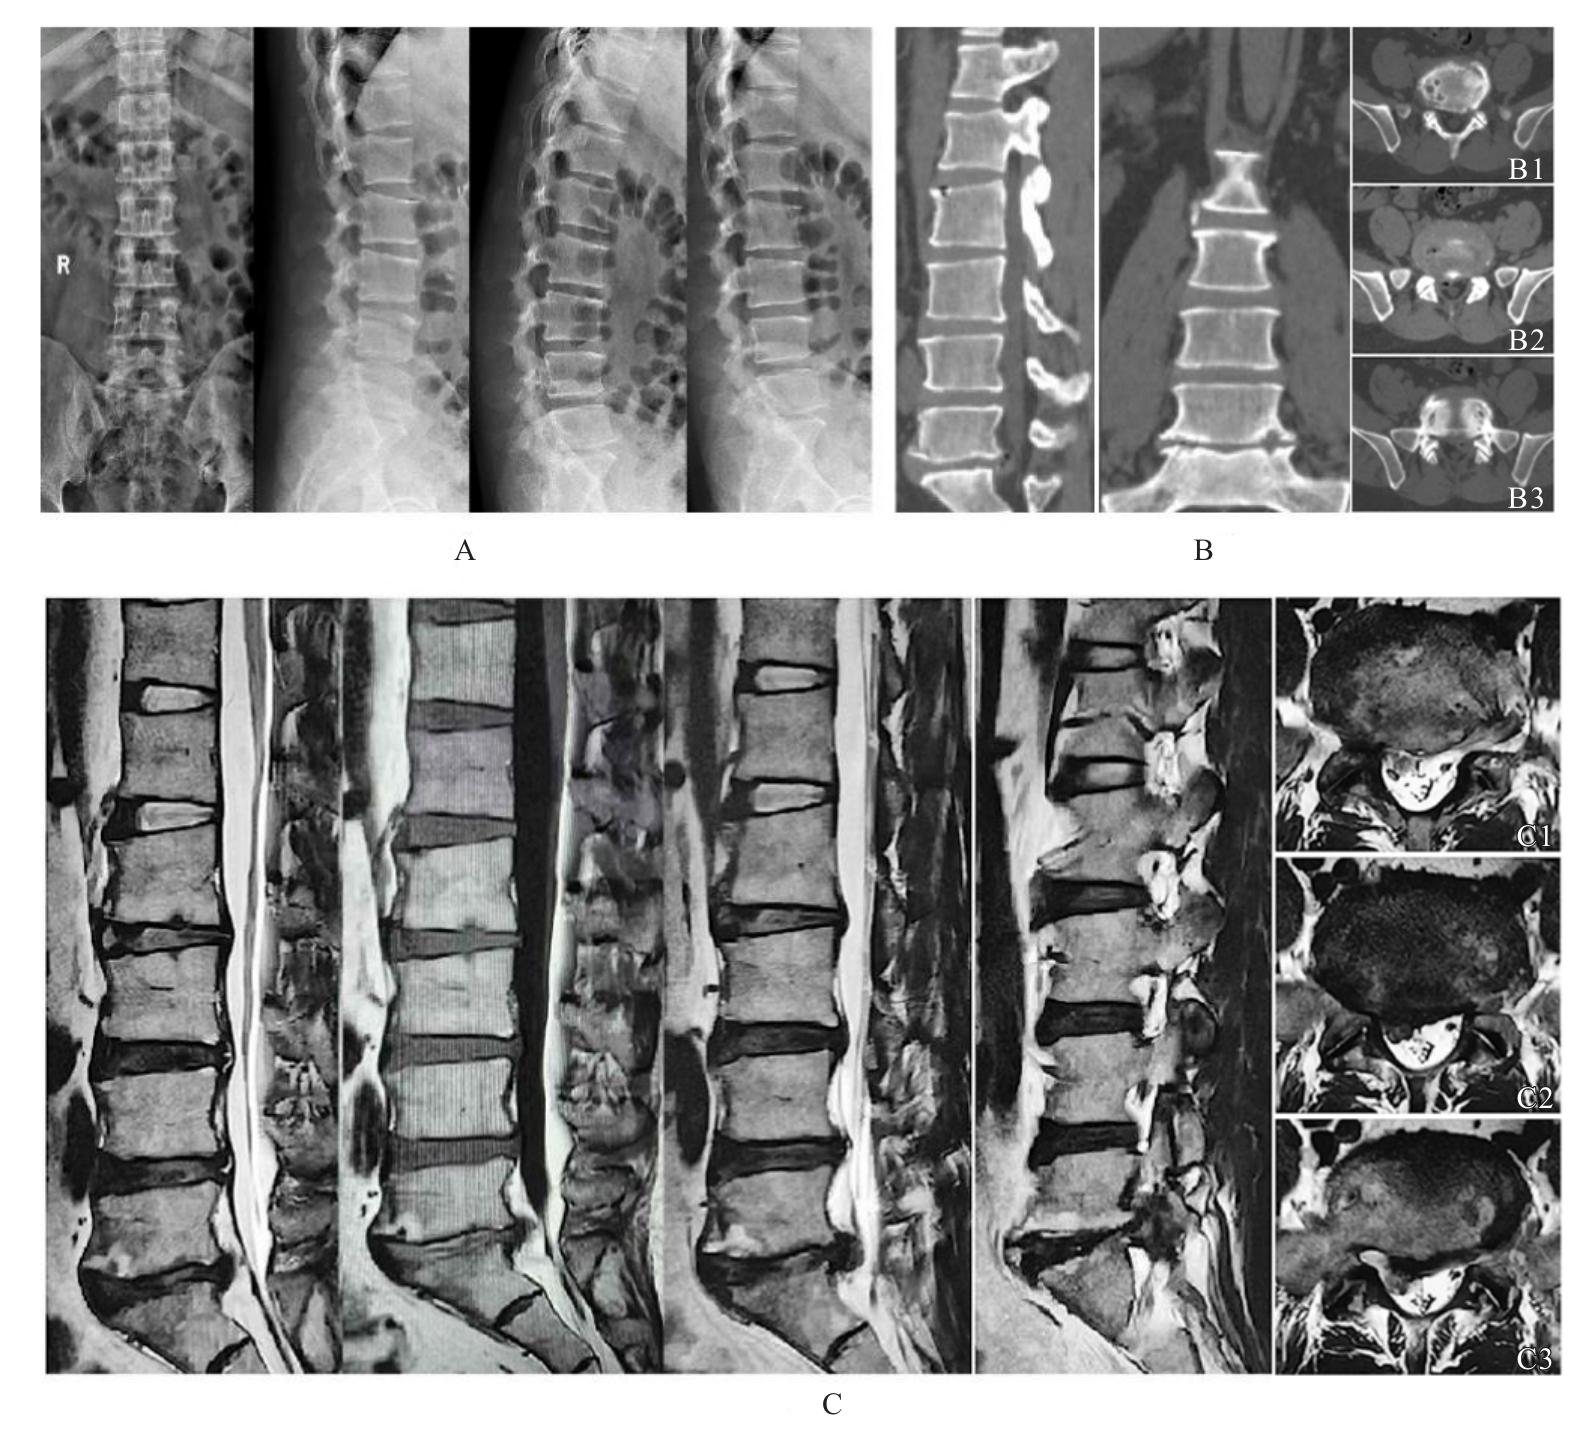

Jing ZENG,Yindong SONG,Zhiguo WANG,Aiju LOU,Dongdong WU,Bing XU,Jiayi LIU,Zili XIONG.

Comparison of clinical efficacy between unilateral biportal endoscopy and percutaneous endoscopic transforaminal discectomy in treatment of lumbar disc herniation

[J]. Journal of Jilin University(Medicine Edition), 2025, 51(5): 1349-1357.